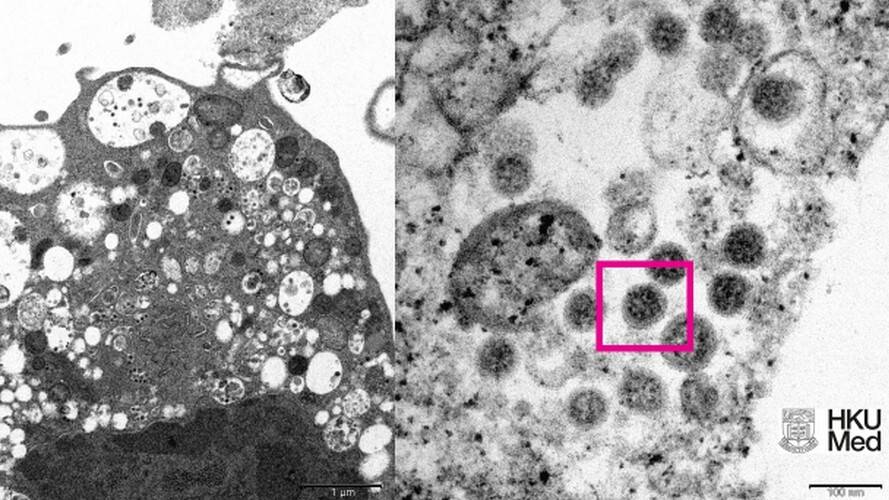

- Изображение штамма "Омикрон" опубликовали учёные из Гонконга